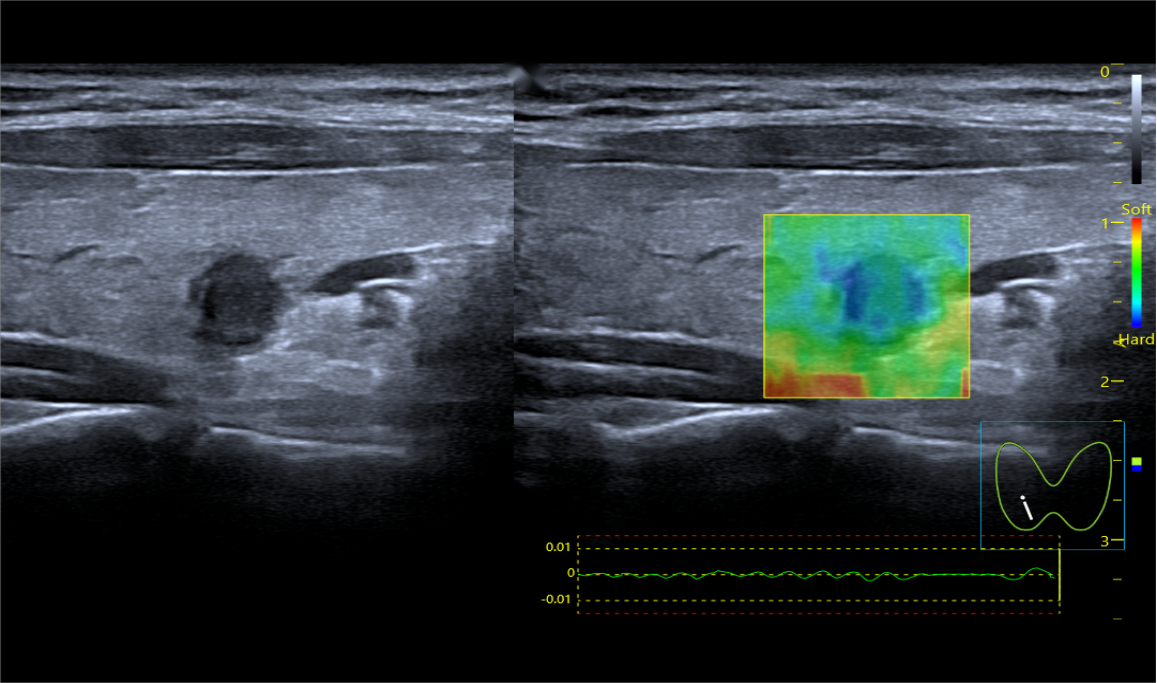

声辐射力弹性成像(ARFI)

Acoustic Radiation Force Imaging: 声辐射力(ARFI)

声能弹性成像也可检测人体组织的软损伤,如早期肌腱拉伤的组织水肿检测,开辟了超声在运动医学领域的研究先河

基于声能 (ARFI)和剪切波波速的实时弹性成像,提供组织软、硬病变的定量评价。

通过自动发射一定能量的声波通过声辐射力直接对所需要检测部位进行激励,用于激励的声波犹如无形的手直接去推动组织产生运动,从而得到表征组织弹性的图像,这种新兴弹性成像技术可以得到更精确的组织应变图像。